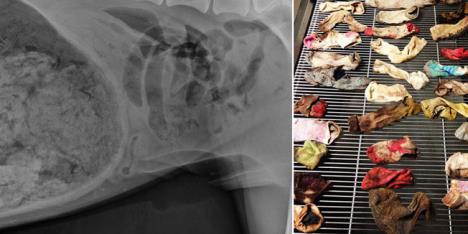

Nakon dvočasovne operacije, dr Ešli Megi je otkrila uzrok bolova: pas je naime progutao ni manje, ni više nego 43 čarape

Pas je poslat na rendgen koji je pokazao prisustvo "stranog tela" u stomaku. Nakon dvočasovne operacije, dr Ešli Megi je otkrila uzrok bolova: pas je naime progutao ni manje, ni više nego 43 čarape.

"Ovo je verovatno najneobičniji slučaj u istoriji ove veterinarske stanice", izjavila je predstavnica bolnice.